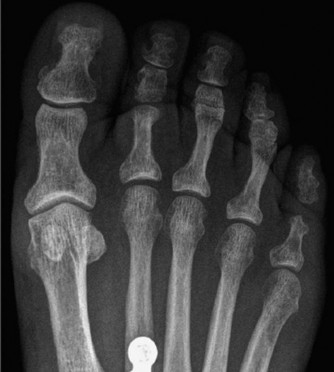

Radiographic evaluation must include weight-bearing anteroposterior (AP), lateral, and oblique views of the foot. On the AP view, the congruency of the medial border of the second metatarsal with the medial border of the middle cuneiform is assessed. On the lateral view, the Meary's angle (the angle between the long axis of the talus and the first metatarsal) is evaluated to quantify sagittal plane collapse. In complex deformities or post-traumatic settings, a non-contrast Computed Tomography (CT) scan is mandatory to map the extent of joint destruction, assess bone stock for hardware purchase, and evaluate for subchondral cysts or avascular necrosis of the navicular.

Reduction of the midfoot deformity must restore the Meary's line on the sagittal plane and close any diastasis between the first and second rays on the coronal plane. Reduction is provisionally held with stout Kirschner wires (K-wires) or reduction clamps.